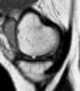

Absent bow-tie sign in knee meniscus